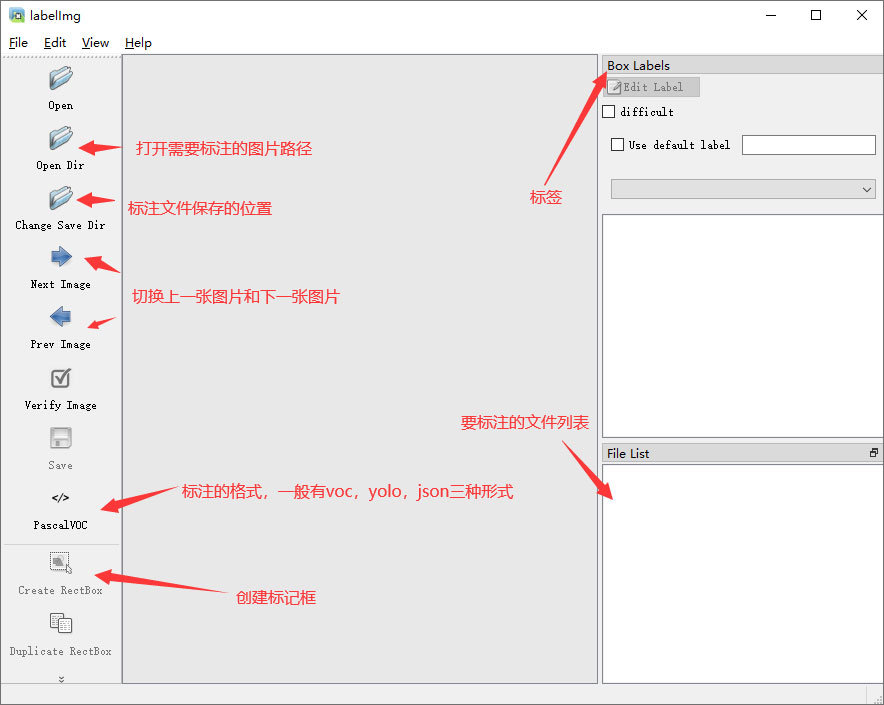

目标检测标注工具

(1)labelimg:开源的图像标注工具,标签可用于分类和目标检测,它是用python写的,并使用Qt作为其图形界面,简单好用(虽然是英文版的)。其注释以 PASCAL VOC格式保存为XML文件,这是ImageNet使用的格式。此外,它还支持 COCO数据集格式。

(2)安装labelimg 在cmd输入以下命令 pip install labelimg -i https://pypi.tuna.tsinghua.edu.cn/simple

结束后,在cmd中输入labelimg

初识labelimg

打开后,我们自己设置一下

在View中勾选Auto Save mode

接下来我们打开需要标注的图片文件夹

并设置标注文件保存的目录(上图中的Change Save Dir)

接下来就开始标注,画框,标记目标的label,然后d切换到下一张继续标注,不断重复重复。

Labelimg的快捷键